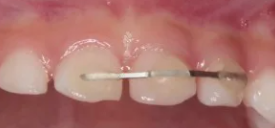

その後、歯のギブス、をつけます。

腕や足の骨を折ったとき、骨が元通りに戻るまで、ギブスをはめますよね?

歯も一緒です。歯のギブスはこちら☆

矯正の装置みたいですが、ケガの治療でもこのような装置を使います。

状態によって、このギブスを、1~3か月したままにしておきます。

そうすると、まわりの組織がどんどん治ってきて、ぐらぐらしていた歯が、揺れなくなってくるのです。